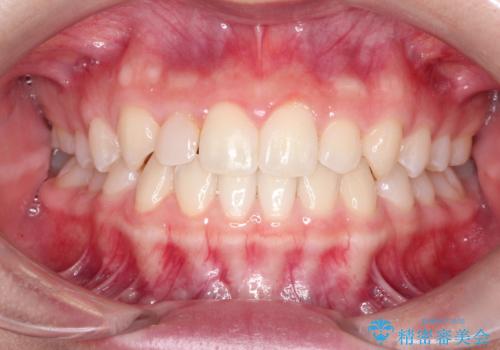

マウスピース矯正とセラミックの組み合わせ治療

- 上の歯の隙間が気になるとのことで来院されました。

上顎の正中に隙間があり、右上の2番目の歯が通常の歯より小さい矮小歯でした。

正中の隙間をインビザライン矯正で閉鎖して、右上の2番目の歯にはセラミックを装着する計画としました。

矯正治療とセラミック治療を組み合わせることにより、審美的により良い結果を得ることができました。